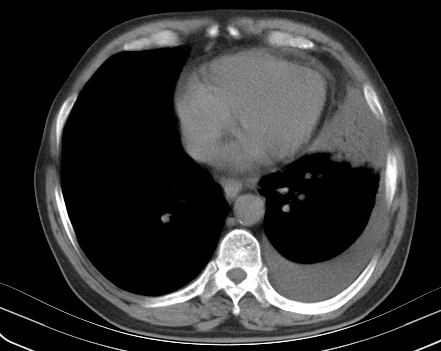

以下是引用老爱克斯新网客在2008-7-31 6:30:00的发言:[br]左肺上叶大片状病灶,左肺上叶支气管狭窄呈鼠尾状,左肺门增大,纵隔内见肿大淋巴结,左侧胸腔积液,余肺清晰。左肺中心型肺癌淋巴结转移,

以下是引用zjzjr在2008-7-31 8:45:00的发言:[br]考虑左侧中心性肺癌伴阻塞性肺炎,左肺上叶肺不张,纵隔淋巴结转移;左侧胸腔积液。建议行纤支镜检查。

以下是引用zjb在2008-7-31 6:32:00的发言:[br]左侧中心性肺癌 阻塞性肺炎 肺不张 胸腔积液 建议气管镜

以下是引用sdzyy在2008-7-31 8:47:00的发言:[br]病灶较治疗前有所进展,胸水增多, 左侧中心性肺癌 并 阻塞性肺炎 肺不张 胸腔积液 可能性大; 建议气管镜检查。 [br] [br]